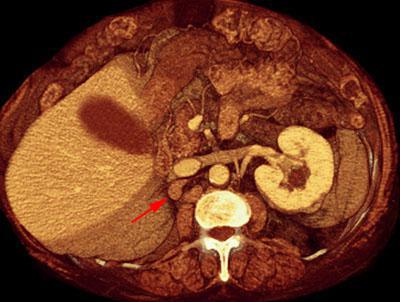

Recidiva local de hipernefroma